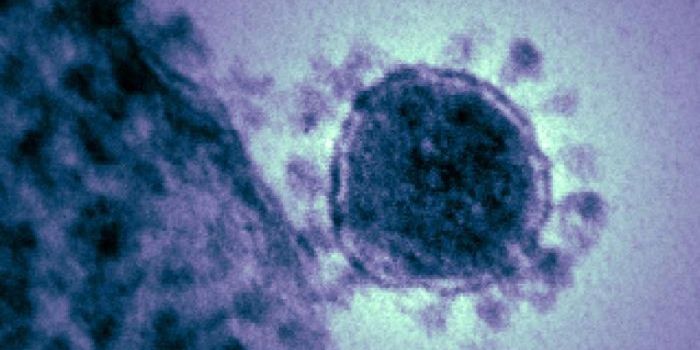

NOV 11, 2021MicrobiologyWhile many people are most familiar with the coronavirus that causes COVID-19, which is called SARS-CoV-2, there are man ...